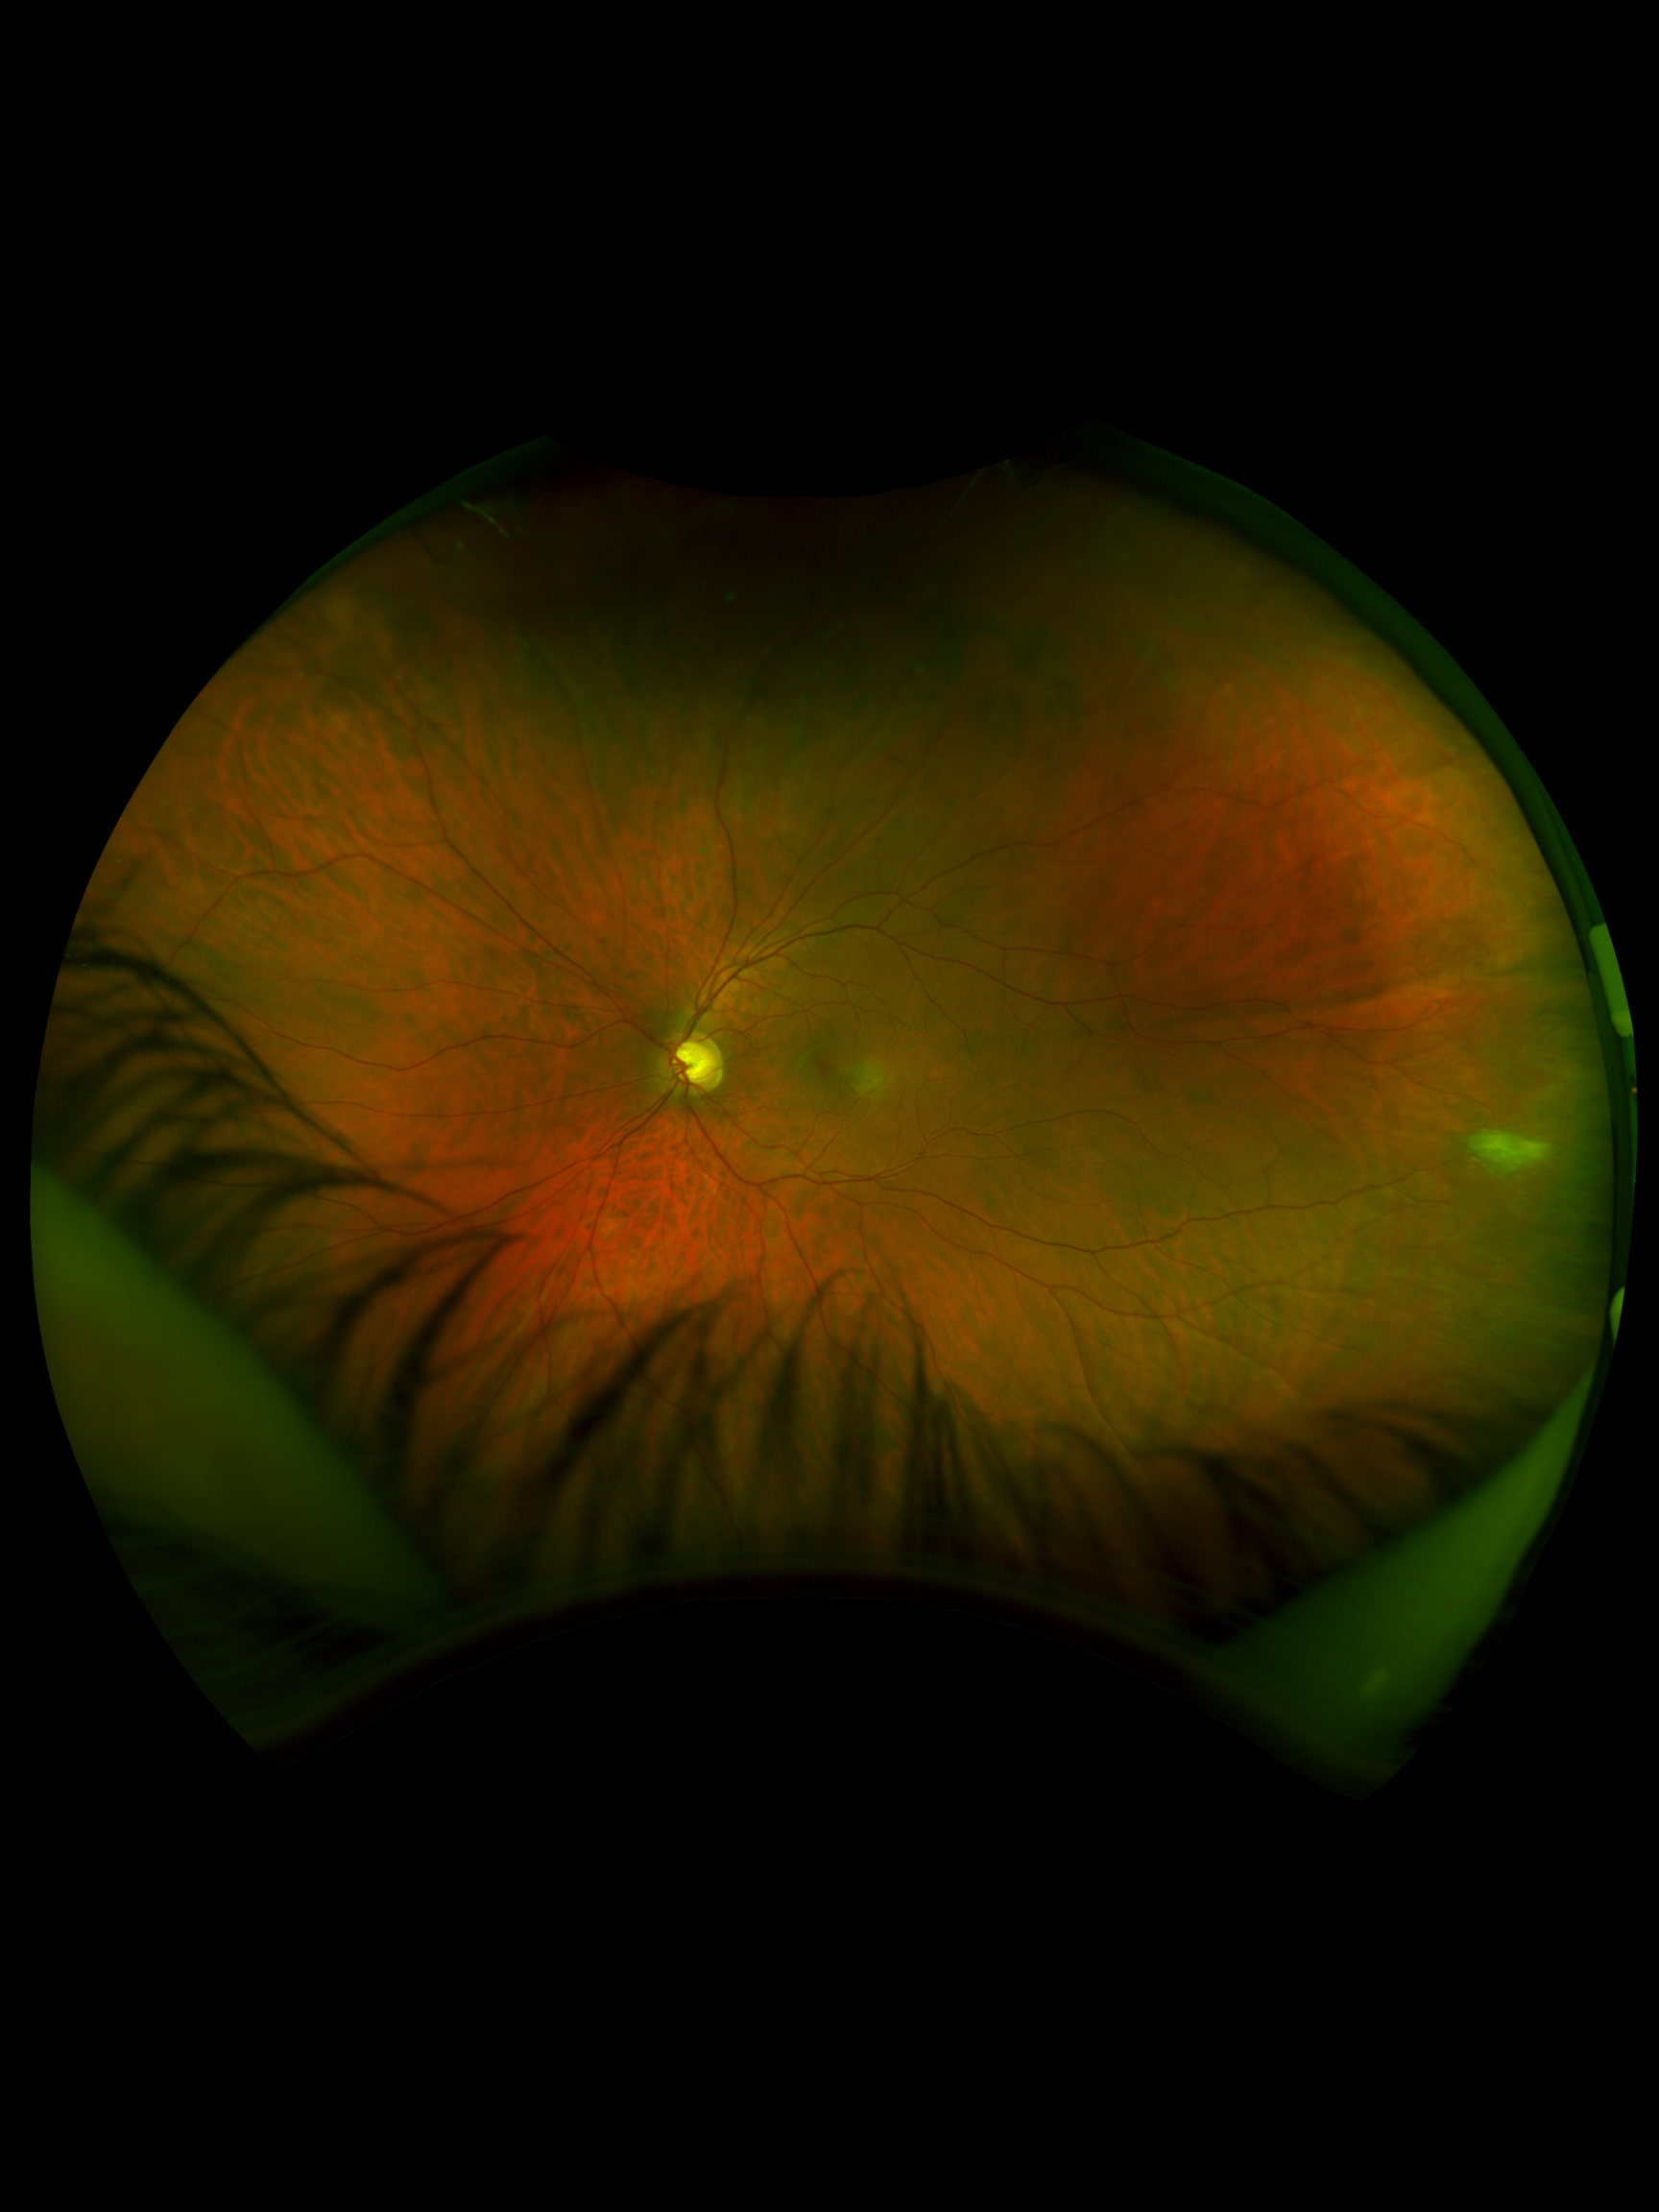

A 37-year-old male was referred for evaluation of a large temporal vitreous tuft OS found during a routine exam. He is asymptomatic with no prior imaging for comparison and a history of LASIK OU. BCVA was not documented. IOPs were 12 mmHg OD and 13 mmHg OS. Anterior segment was largely unremarkable aside from trace blepharitis and mild pigment findings OD. Posterior segment showed healthy discs with C/D ratios of 0.65 OD and 0.60 OS. Peripheral exam revealed a large vitreous tuft with traction at 3 o’clock OS.

The findings are consistent with a vitreous tuft rather than a retinal tear, and immediate treatment is not required. These lesions are typically benign but may warrant monitoring due to their association with vitreoretinal traction. Referral for a non-urgent in-person retinal evaluation is reasonable to confirm the diagnosis and counsel the patient. Continued observation with routine follow-up is appropriate, with education on symptoms of retinal complications.

Vitreoretinal tufts are peripheral retinal abnormalities characterized by focal vitreous adhesion and retinal gliosis. They are often discovered incidentally during dilated fundus examination and may be associated with increased vitreoretinal traction. While generally benign, they can occasionally predispose to retinal breaks under tractional forces.